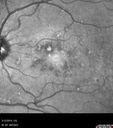

45 year old man was told to come in because of ‘white spots on their retina’. He now has to take his glasses off to read labels. He has always had trouble with oncoming headlights messing up his vision for a short time. VA OD: cc20/20 NscJ1 OS: cc20/20 NscJ1+ Pisciform lesions in the macula of both eyes.

Fundus Flavimaculatus - Asymptomatic - Color Photo809 views45 year old man was told to come in because of ‘white spots on their retina’.